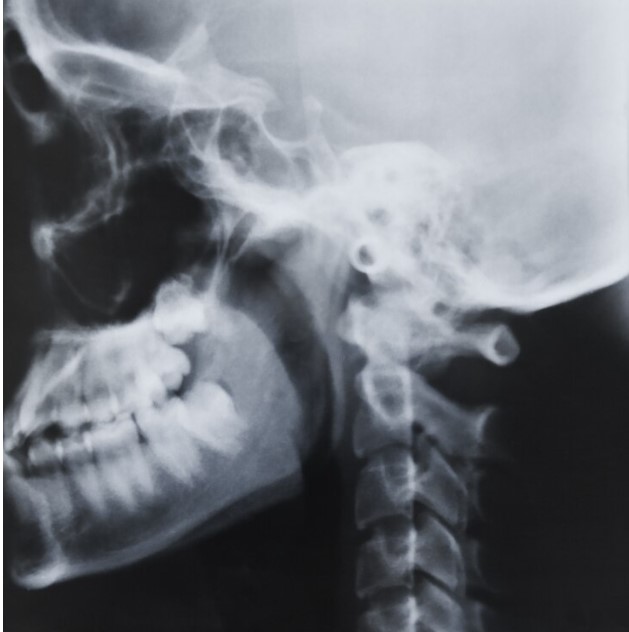

Основой диагностики патологий носоглотки служит рентген околоносовых пазух – исследование, основанное на проникающей способности жесткого ионизирующего излучения.

Проходя через костно-хрящевые структуры и мягкие ткани, рентгеновские лучи образуют специфический рисунок на фотопленке или чувствительном экране цифрового аппарата.

Изображение отражает особенности строения носоглоточных и лобных полостей, носовых ходов и других анатомических элементов исследуемой области.

На основании полученных снимков ЛОР-врач ставит диагноз и определяет наилучшую схему лечения.

• Меняя положения головы, выполняют снимки в четырех проекциях – боковой, подбородочно-черепной, задне-передней и позиции Уотерса.

Рентгеновские снимки носовых пазух позволяют обнаружить ряд заболеваний, требующих немедленного лечения:

• воспалительные процессы слизистой оболочки, скопления гноя, характерные для гайморитов, синуситов, фронтитов;

• заполнение пазух экссудатом;

• наличие полипов, кист или злокачественных опухолей;

• врожденные или приобретенные деформации носовой перегородки;

• другие аномалии носовых дыхательных ходов;

• последствия травм носа, лба или челюсти – трещины и переломы костей;

• наличие инородных тел (актуально для детей).

Снимки, сделанные в нескольких проекциях, создают наиболее полную картину патологических изменений исследуемой области.

Рентгеновское исследование пазух носа – это безболезненная процедура, для выполнения которой необходимо посетить специальный кабинет клиники, оснащенный соответствующим оборудованием. Обследование назначает лечащий ЛОР-врач. Снимки обязательно выполняются в нескольких проекциях, чтобы лучше выявить патологические процессы или травматические повреждения. При проведении диагностики рентгенолог выбирает позиции, позволяющие наиболее полно отобразить особенности внутреннего строения носо-лобной области.